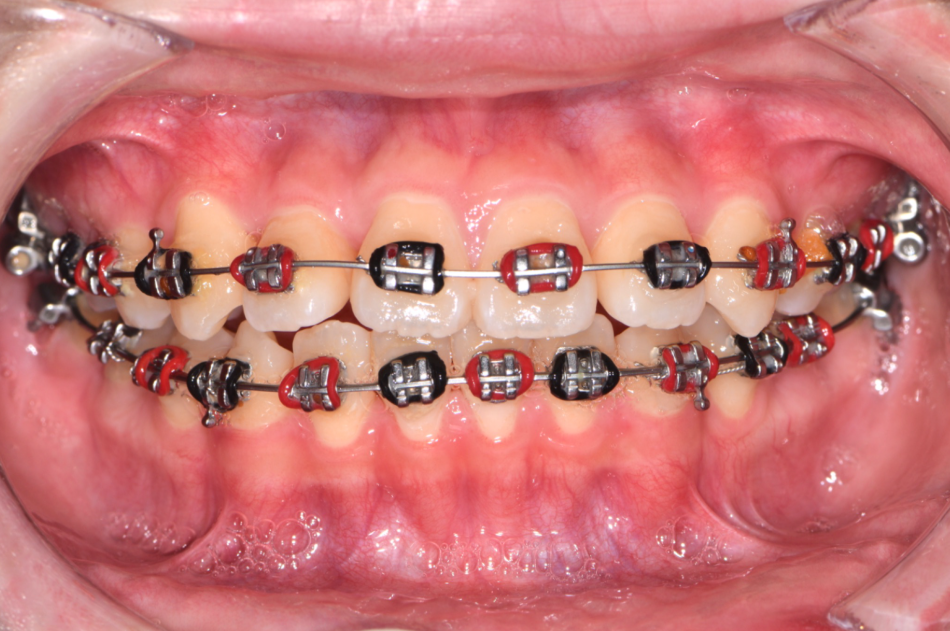

金屬矯正

金屬矯正是歷史最悠久的矯正方式,適合正在換牙或恆牙初期的孩子。金屬矯正器治療效果穩定明確,使用鐵絲、橡皮筋慢慢讓牙齒回復到正確的位置,為孩子打造健康、整齊笑容。還有鮮豔橡皮圈,讓孩子充滿參與感!

患者小朋友是休士頓火箭隊小小球迷,選擇了象徵火箭隊紅黑的橡皮圈,為治療增添趣味!